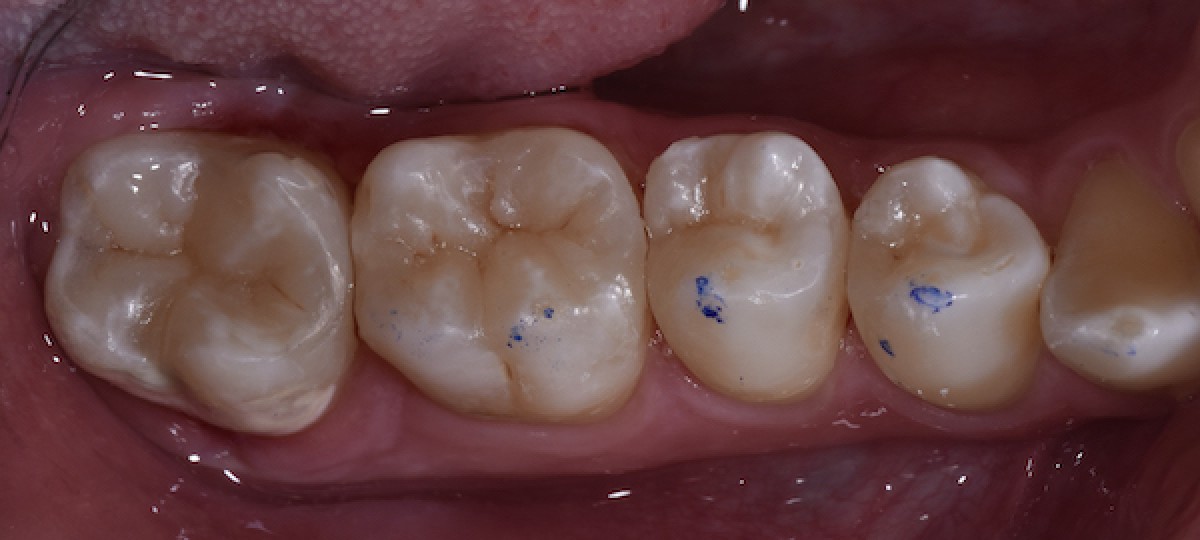

Clinical examination revealed enamel hypoplasia of 4.7 and irregular contact point between 4.6 and 4.7 that was causing food impact. Rx examination (orthopantomography and bitewings) and vitality test were carried out and all elements were confirmed to be vital.

The diagnosis was the following: incongruous restoration of 4.7, primary caries on 4.6, 4.5 and 4.4. According to the fact that the patient was very young, a minimally invasive approach with only direct restorations was proposed and accepted by the patient.

Oral hygiene motivation was carried out, alongside with proper periodontal treatment (scaling, polishing) before taking initial photo (Fig.1).